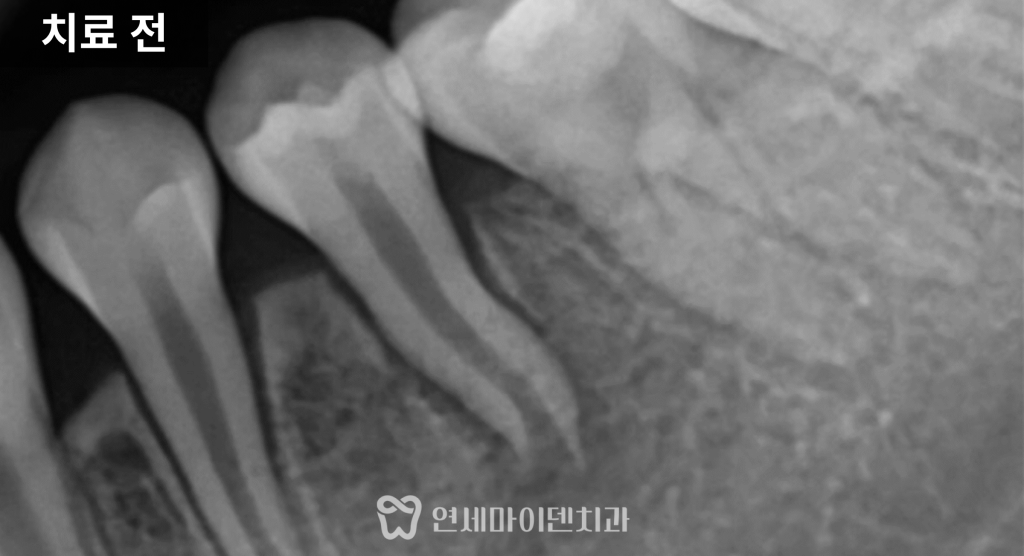

엑스레이를 확인해보니

해당 치아는 뿌리 끝이 완전히 닫히지 않은

성장 중인 상태였습니다.

하지만 충치는 보이지 않았음에도

뿌리 주변 뼈가 녹아 있는

염증 소견이 확인되었습니다.

이처럼 겉으로 충치가 없는데도

신경이 손상되는 경우가 있습니다.

이번 케이스의 원인은

‘치외치(치아 안에 또 다른 치아 구조가 있는 경우)’였습니다.

치아 내부에 형성된 구조가

뿔처럼 돌출되어 있다가

어느 순간 부러지면서

신경이 구강 내로 노출되고

세균이 침투해 신경이 괴사된 상황이었습니다.

이 과정에서 통증 없이 진행되다가

뒤늦게 흔들림과 염증으로 나타나는 경우도

적지 않습니다.